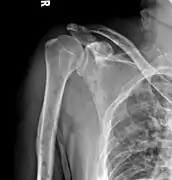

The diagnostic examination of a person with suspected multiple myeloma typically includes a skeletal survey. This is a series of X-rays of the skull, axial skeleton, and proximal long bones. Myeloma activity sometimes appears as "lytic lesions" (with local disappearance of normal bone due to resorption) or as "punched-out lesions" on the skull X-ray ("raindrop skull"). Lesions may also be sclerotic, which is seen as radiodense.[64] Overall, the radiodensity of myeloma is between −30 and 120 Hounsfield units (HU).[65] Magnetic resonance imaging is more sensitive than simple X-rays in the detection of lytic lesions, and may supersede a skeletal survey, especially when vertebral disease is suspected. Occasionally, a CT scan is performed to measure the size of soft-tissue plasmacytomas. Bone scans are typically not of any additional value in the workup of people with myeloma (no new bone formation; lytic lesions not well visualized on bone scan).

X-ray of the forearm, with lytic lesions

Multiple myeloma in the upper arm